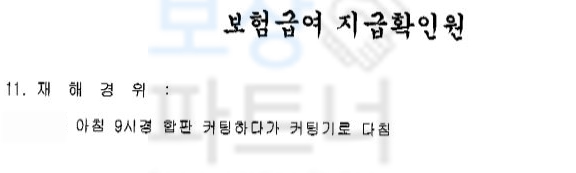

차@@님은 싱크대 공장에서 작업하시던 중 톱날에 장갑이 말려들어가며

엄지손가락이 분쇄 골절의 형태로 골절되는 사고를 당하셨습니다. 아래의 사진은 사고 당시 엑스선 사진입니다.